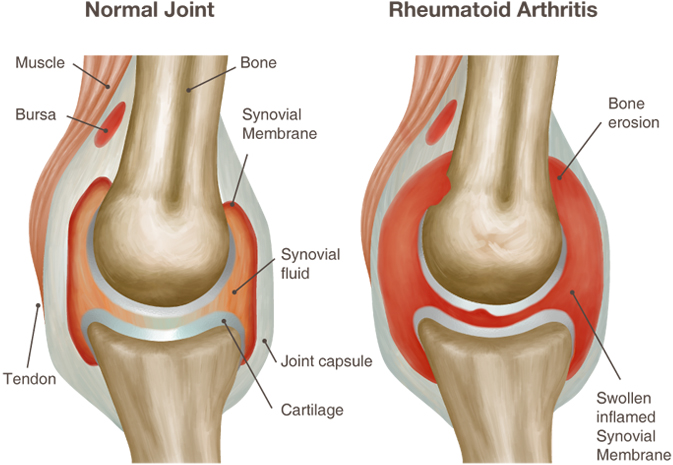

Медицинские состояния: Септический артрит коленного сустава